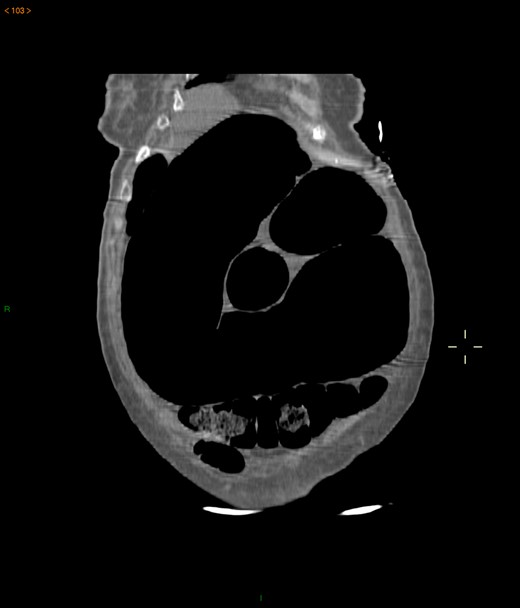

Case 2: A 92-year-old women, without previous abdominal surgery or history of abdominal trauma or peritoneal infections was admitted to the emergency department with generalized abdominal pain. Physical exam revealed markedly distended abdomen with generalized abdominal pain with tenderness. Laboratory investigation on admission: white cell count of 30.200/mm3 with 84.7% neutrophils, protein C reactive of 13.6 mg/dL and lactates of 2.17 mmol/l. Abdominal X-ray showed a marked colonic enlargement. Abdominal-pelvic CT identified a colonic volvulus associated with a transmesocolic hernia with transmural necrosis of the colon sigmoid (Figs 2 and 3). The patient was proposed to laparotomy during which a volvulus of colon sigmoid with transmural necrosis in a strangulated transverse transmesocolic and transomental (great omentum) hernia was identified (Figs 4 and 5). A Hartmann procedure was conducted and the patient was discharged at fifth post-operative day. At 3 months follow-up consultation, the patient remained free of complains.

Abdominal-pelvic CT—coronal plane: colonic volvulus associated with a transmesocolic hernia with transmural necrosis of the colon sigmoid.